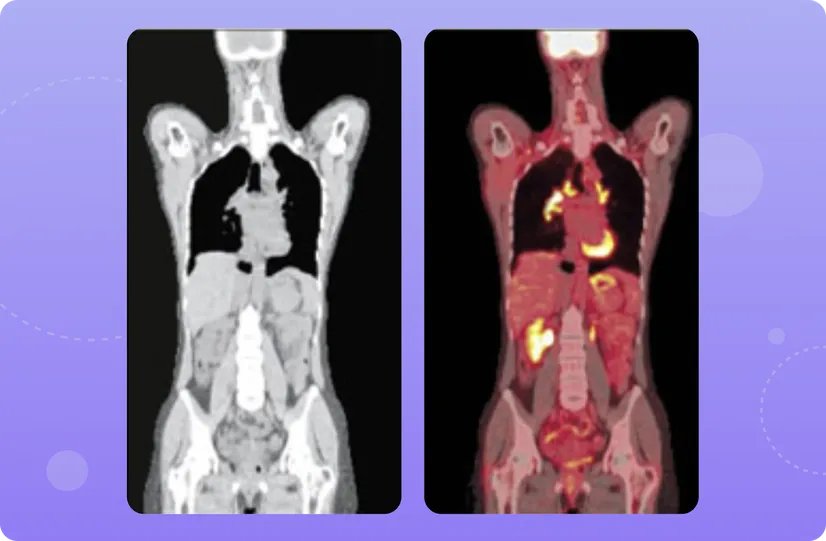

ПЭТ/КТ — это способ визуализации опухолей, сочетающий сразу две методики: позитронно-эмиссионную томографию (ПЭТ) и компьютерную томографию (КТ).

КТ в этом случае создает изображение внутренних органов, кровеносных сосудов, патологических образований, а ПЭТ показывает активность биологических процессов в этих тканях1.